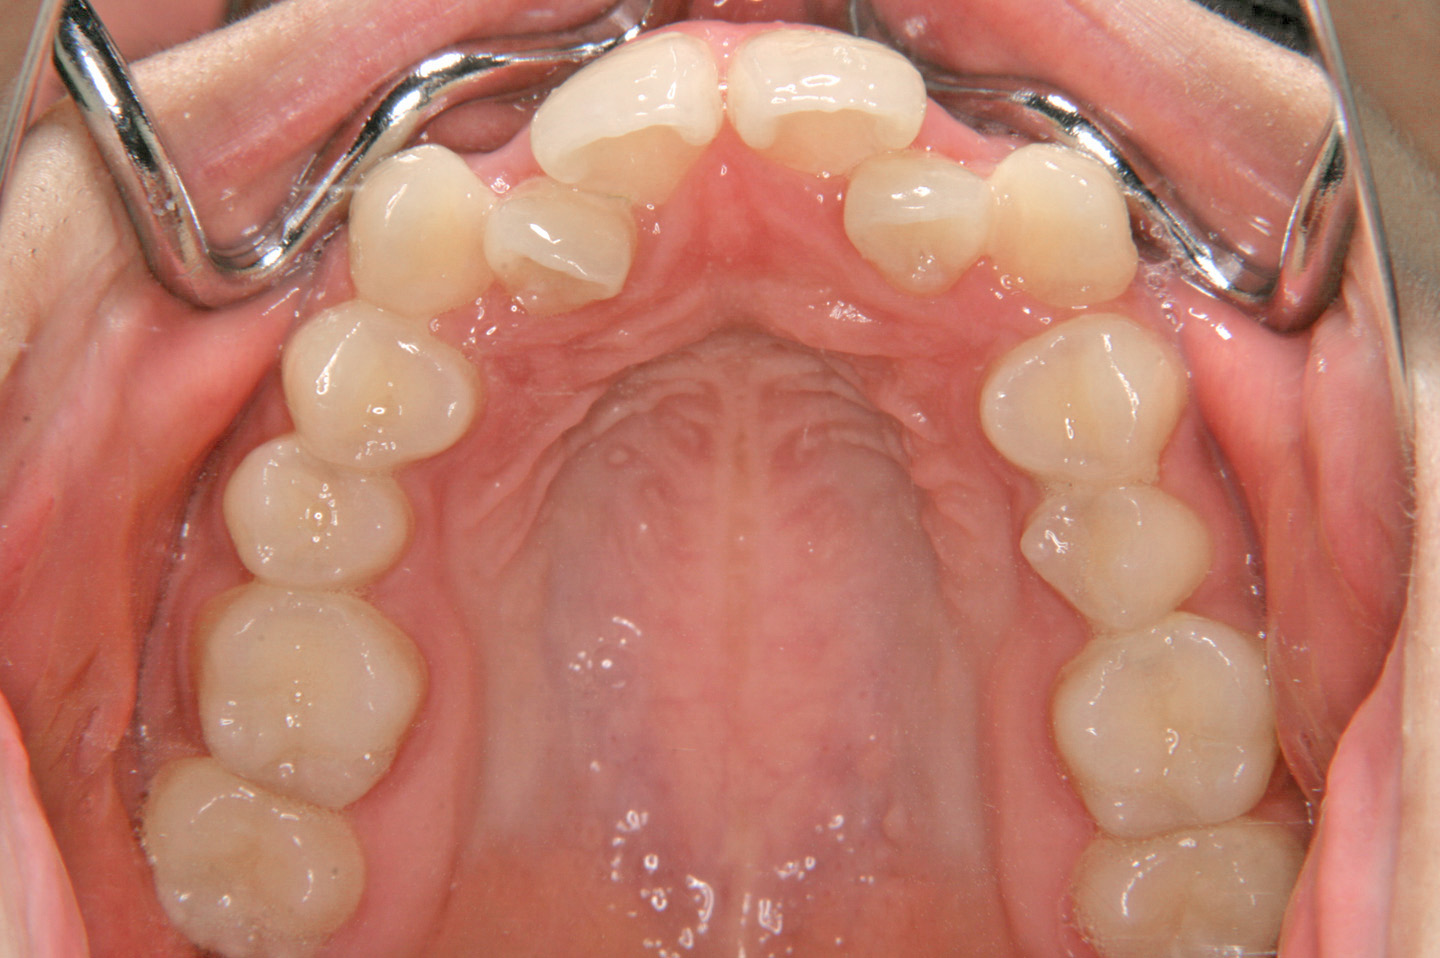

上顎前突(出っ歯)

叢生(乱ぐい歯)

歯のデコボコを気にされて来院された15歳の女子の患者さんです。歯のデコボコの程度が強く上顎の前突傾向があったため、上顎小臼歯を抜歯させていただきエッジワイズ装置を用いて治療させていただきました。途中、顎間ゴムをご協力いただき、口元の前突感を改善することができました。現在、上下ともにボンデッドワイヤーとリテーナーを併用した保定期間に移行しております。